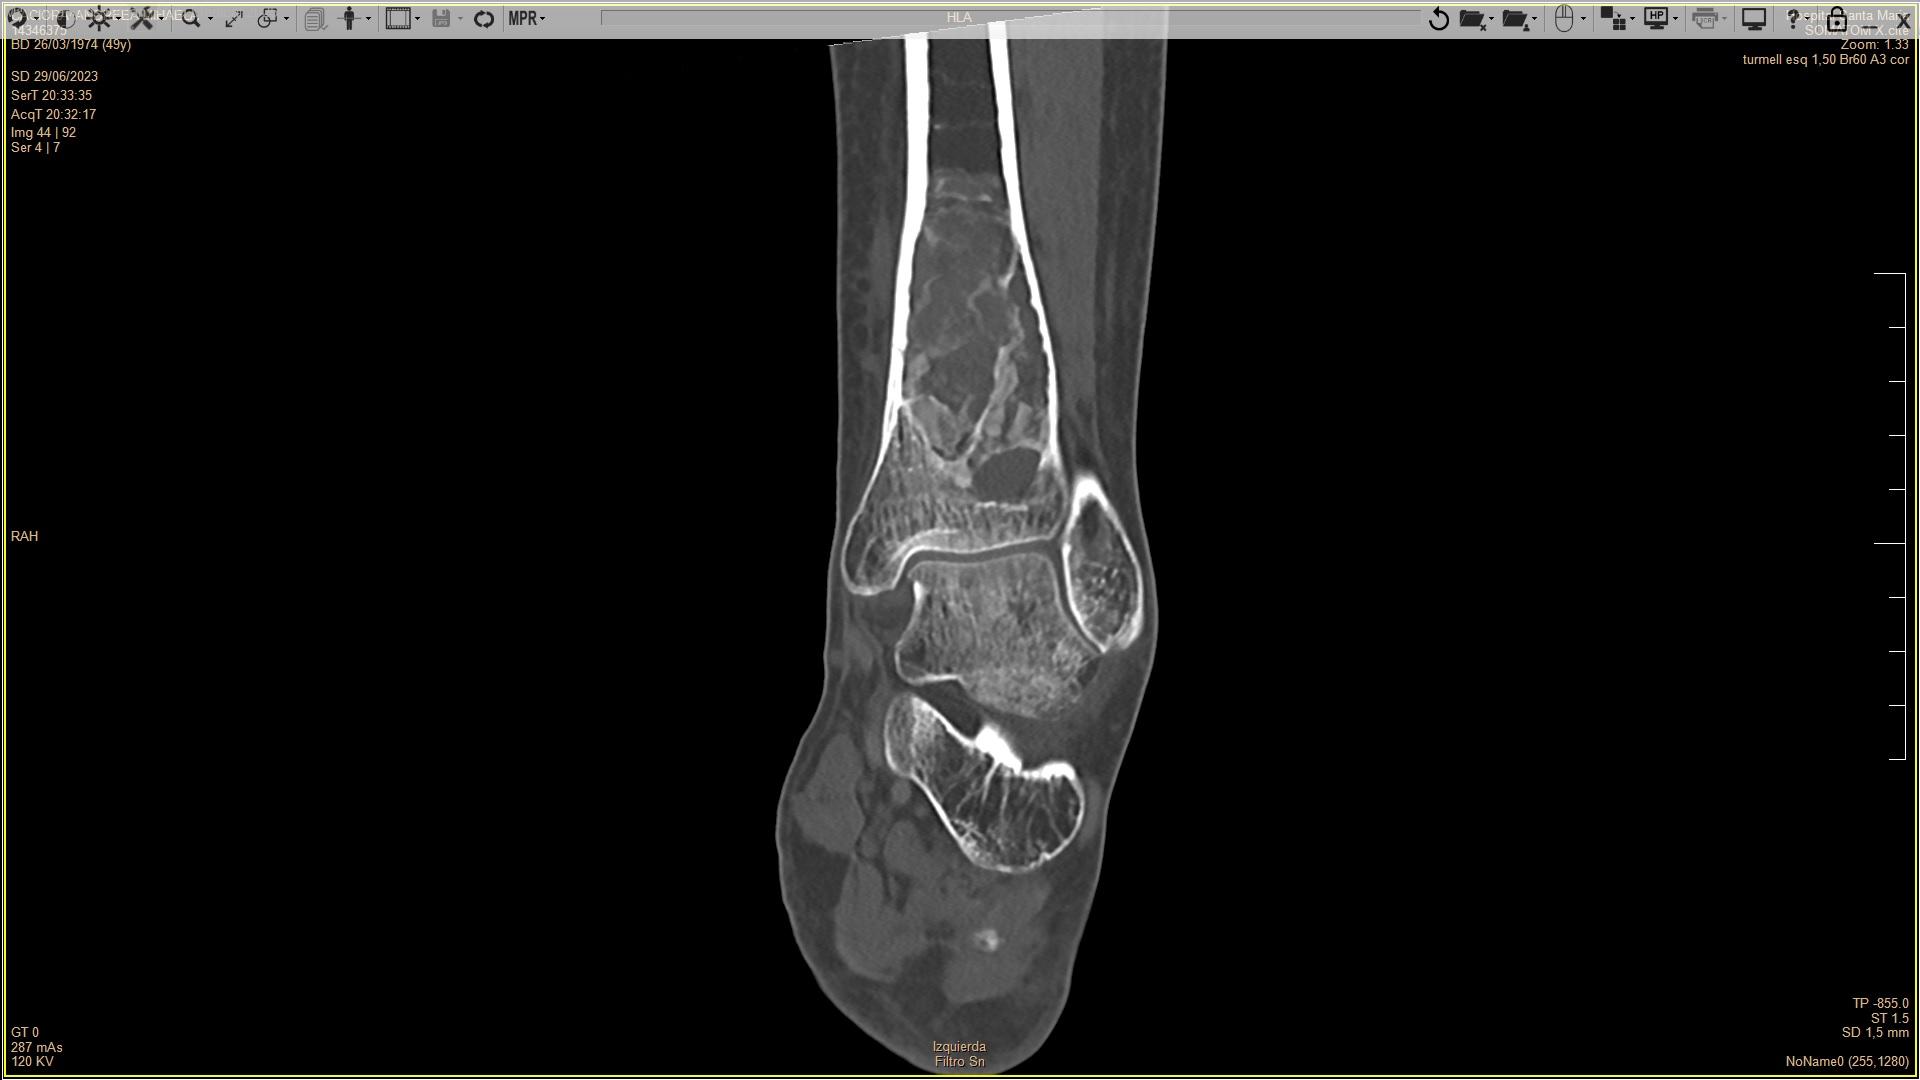

Quiste óseo aneurismático vs células gigantes multinucleadas de tipo ostoclasto. A propósito de un caso

Paciente de 50 años sin alergias medicamentosas conocidas y sin antecedentes clíncos de interés prestentó clínica de dolor e impotencia funcional en tobillo izquierdo. Se realizó una radiografía donde se apreciaba una tumoración ósea en tibia...